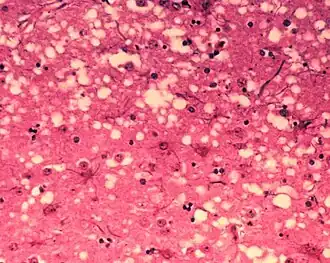

Diagnosis of BSE continues to be a practical problem. It has an incubation period of months to years, during which no signs are noticed, though the pathway of converting the normal brain prion protein (PrP) into the toxic, disease-related PrPSc form has started. At present, no way is known to detect PrPSc reliably except by examining post mortem brain tissue using neuropathological and immunohistochemical methods. Accumulation of the abnormally folded PrPSc form of PrP is a characteristic of the disease, but it is present at very low levels in easily accessible body fluids such as blood or urine. Researchers have tried to develop methods to measure PrPSc, but no methods for use in materials such as blood have been accepted fully.

The traditional method of diagnosis relies on histopathological examination of the medulla oblongata of the brain, and other tissues, post mortem. Immunohistochemistry can be used to demonstrate prion protein accumulation.[26]